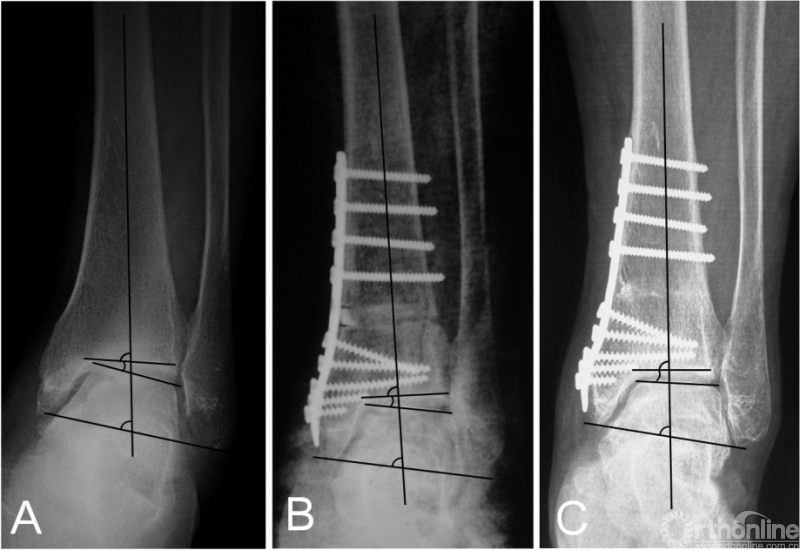

在踝上截骨时,是否及何时需要辅助腓骨截骨目前尚无定论。在早期的报道中,腓骨截骨被要求作为常规术式来矫正踝关节内翻畸形[19-21];然而,后来的一些研究则要求在所有患者中保留腓骨[6,11,13,15]。而我们只在需要时才辅助腓骨截骨,评估内容分为术前和术中。术前评估包括:1)患侧TC角较健侧减小超过5°或存在内翻改变;2)存在腓骨骨折畸形愈合;3)患者因胫骨骨骺损伤史而导致腓骨相对较长。术中主要评估在胫骨远端关节面积距骨复位时,是否存在外侧阻挡。生物力学研究指出,在胫骨远端关节面外翻时,胫距关节的接触压强并未随之显著外移,而是在内侧形成峰值压强;只有在腓骨截骨后,胫距关节的接触压强才随着外翻角度的增大逐渐转向外侧[24]。因此,在这种情况下,腓骨截骨可以促进关节协调性的恢复,以及接触压力的外移[12]。根据我们的研究结果,腓骨截骨组的患者,TT角的改善程度更加显著(图3)。尽管两组的术后平均TT角基本一致,这正说明在腓骨截骨组,患者的术前内翻畸形更加显著。另外,我们的研究也发现腓骨截骨组的TC角改善更加明显。

图3 术前X线片提示内翻型踝关节骨关节炎(3B期),行踝上截骨合并腓骨截骨术后2年,患者的关节匹配度及负重力线均矫正良好,距骨倾斜角从术前的14.5°降至1.2°。

踝上截骨的主要目标之一就是矫正冠状面内翻畸形,即TAS角。临床研究指出,TAS的平均矫正程度从8.5~14.5°不等[6-21]。而对于踝关节OA患者矢状面TLS角为何会减小目前仍无定论[20,21]。本研究的TSA角在术前与术后未获得显著性差异,这可能与部分患者术前踝关节前侧存在显著骨赘有关(图4),因此术前的TLS测量常不能反映真实的TLS情况。因此,我们认为除非存在显著改变,术中无需刻意的去矫正TLS角。关于TT角在踝上截骨术中的意义目前争论最为激烈,研究报道间的差异性较大。一些作者指出,术后TT角得到显著矫正[8,11,13,16,17];然而,一些作者却强调踝上截骨并无矫正TT角的能力[6,12,14,21]。Tanaka等[21]报道的病例中,所有术前TT≥10°的患者,术后均未矫正至正常。Lee等[14]指出,术前TT角与术后TT角有相关性,他们认为在术前TT≥7.3°的患者,应放弃踝上截骨术。然而,在我们的患者中,67%(4/6)术前TT≥10°的患者,术后恢复到正常范围(TT≤4°[12])。Mann等[15]报道,在术后TT≥10°的患者,依然可以获得较好的临床功能。Kim等[11]则报道,没有任何影像学指标与术后功能有直接相关性。我们认为,在非终末期内翻型踝关节OA患者,通过踝上截骨来矫正负重力线及改善关节适配性是值得的,即使对于TT较大的患者。因为踝上截骨可以关节接触压强得到重新分布,外移踝关节机械轴[28],延缓甚至逆转OA的进程;甚至通过术后负重改变,使TT重新恢复至正常范围(图5)。我们认为,影像学的改变有时是需要时间的,正如OA的形成原因。Cheng等[7]报道,所有患者在随访时内侧间隙逐渐增宽,且常需要1年以上时间才能使踝关节间隙改善至理想程度。

图5术前的距骨倾斜角(TT)为10.7°(5A),术后矫正至7.8°(5B);然而术后32个月随访时TT则已经恢复至1.5°(5C)。